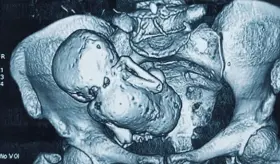

La gota es una enfermedad sistémica que puede afectar diferentes partes del cuerpo debido a la acumulación de urato monosódico en los tejidos.